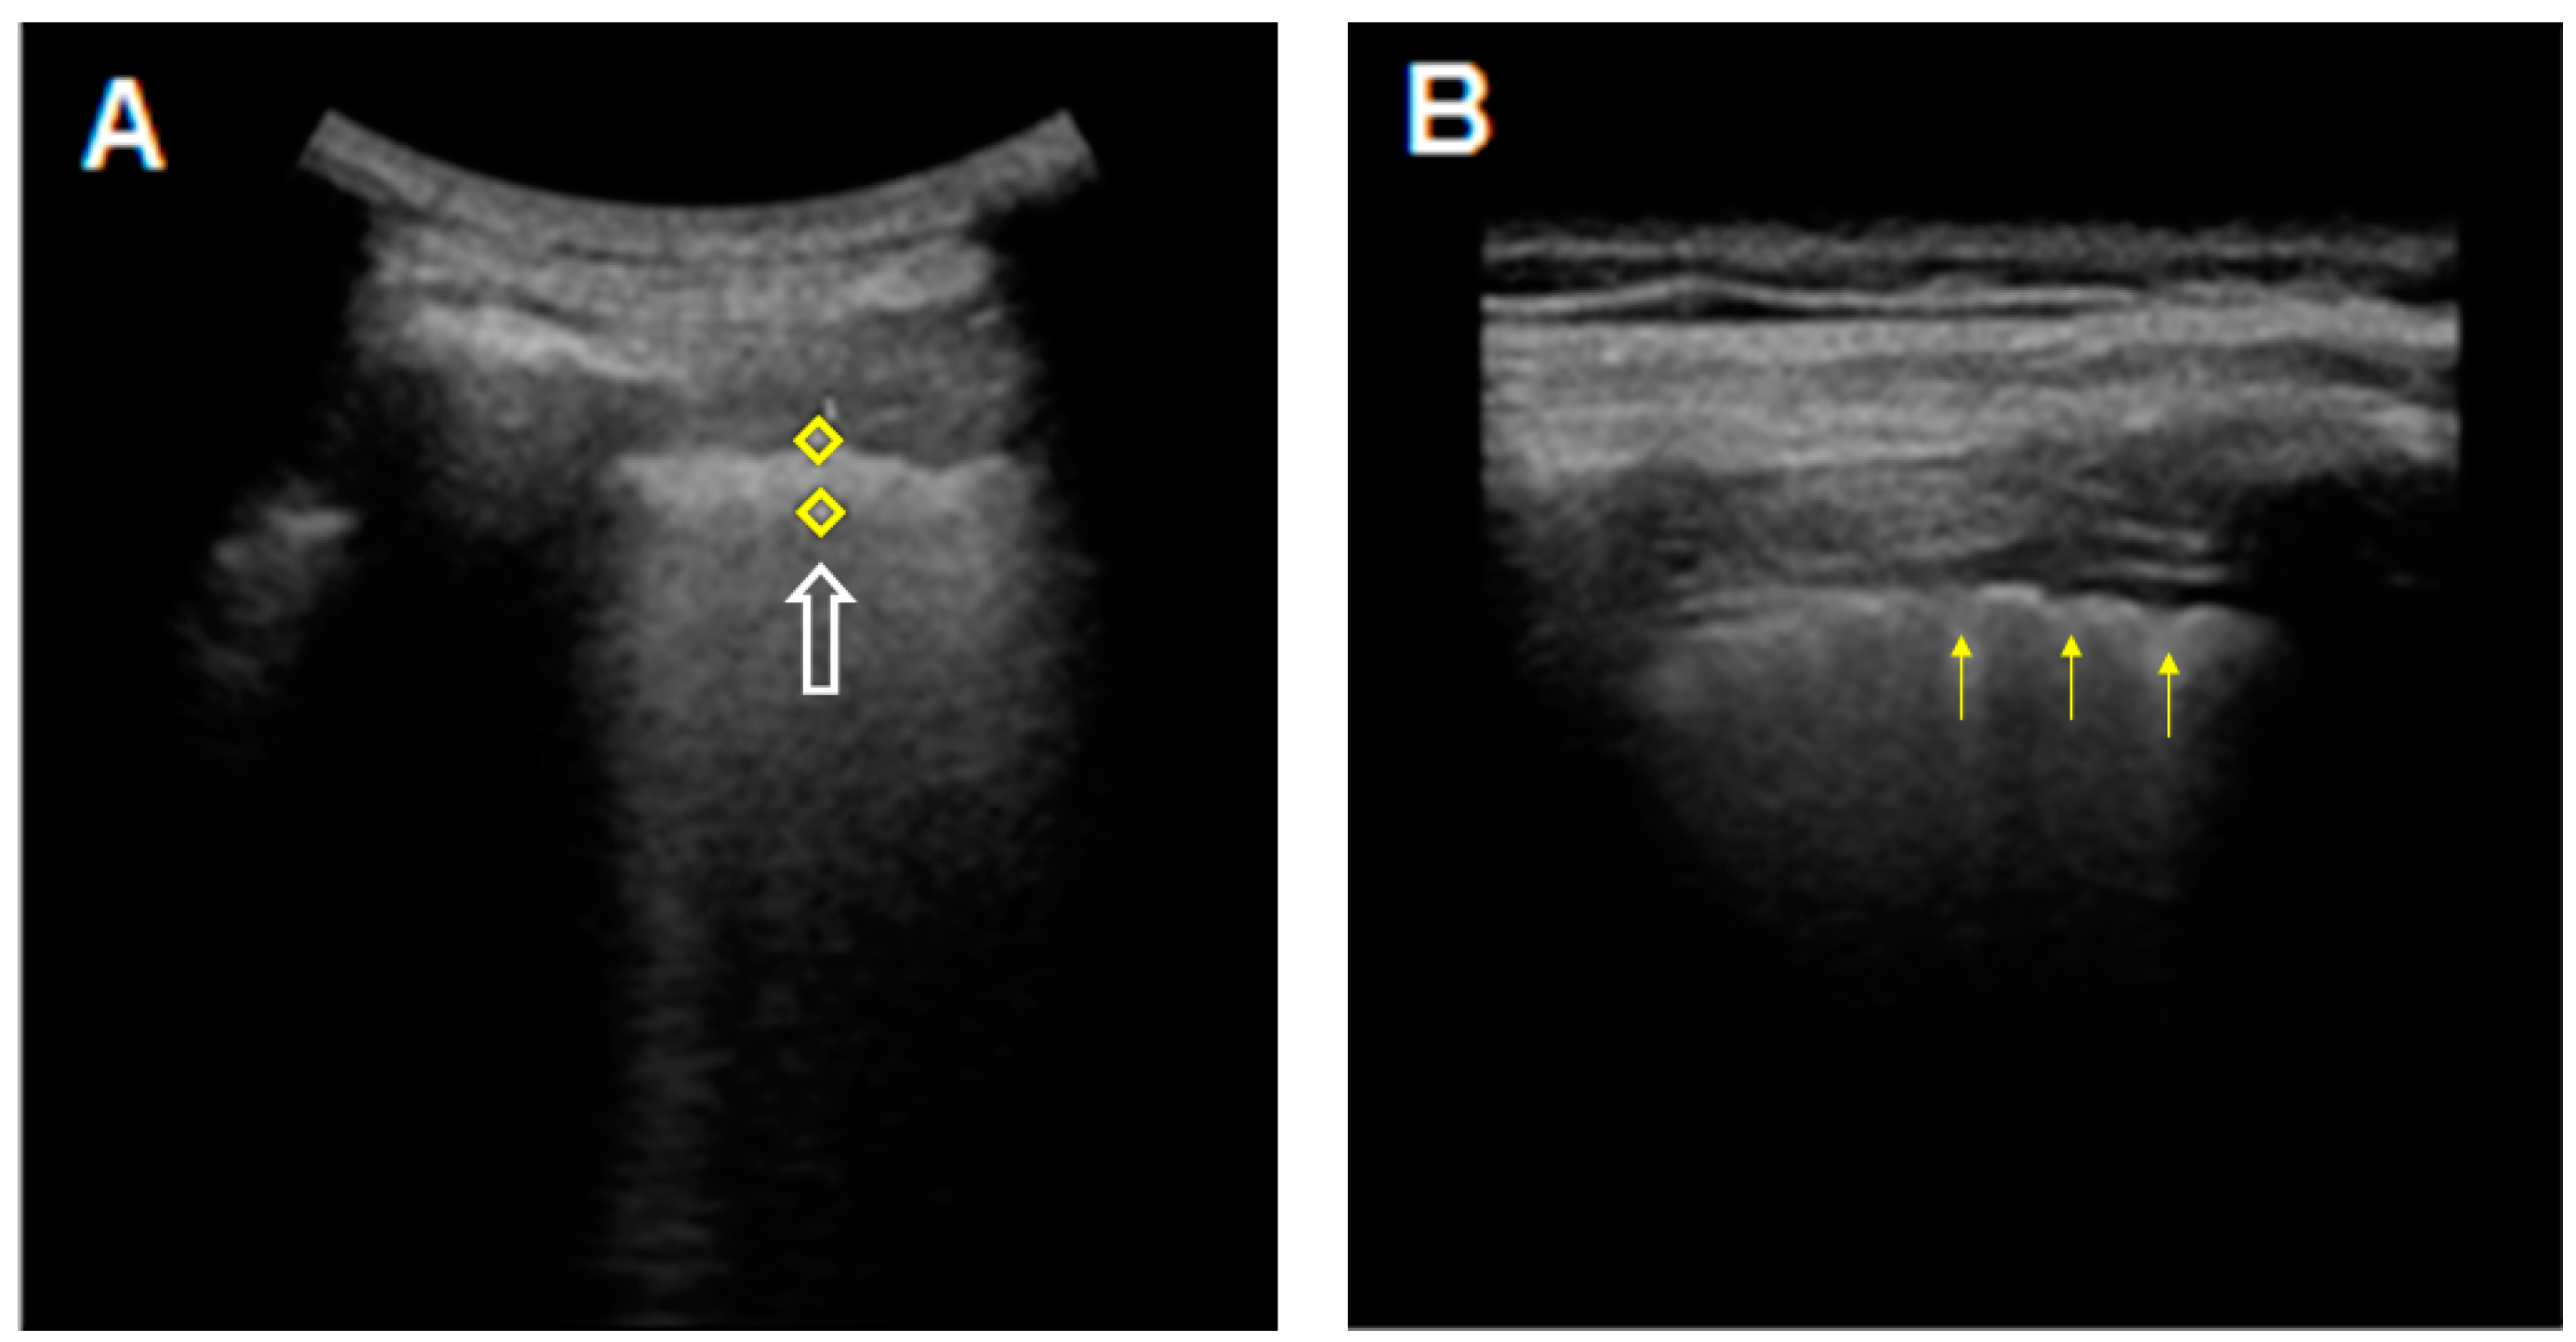

| Ultrasound findings, n (%) | |

| Thickness of the pleural line (>3 mm) | 43 (100%) |

| Irregular/fragmented/blurred pleural line | 42 (98%) |

| >3 B-lines | 38 (86%) |

| Subpleural nodes | 32 (74%) |